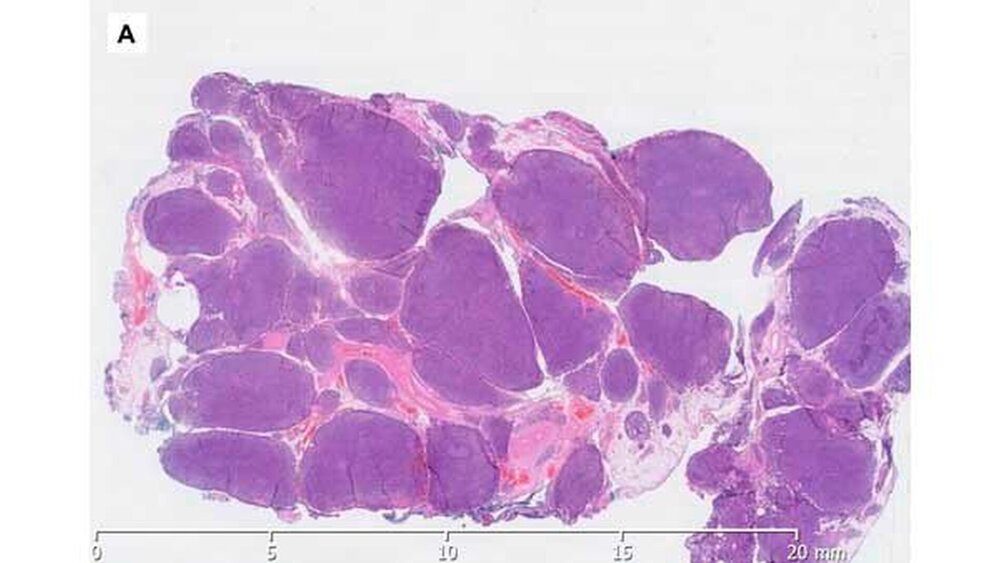

Nach den üblichen präoperativen Narkosevorbereitungen führten wir die Exstirpation der Glandula sublingualis in Intubationsnarkose unter stationären Bedingungen durch. Der Eingriff selbst sowie der unmittelbare postoperative Verlauf gestalteten sich regelrecht, so dass die Patientin bereits am Folgetag in unsere ambulante Nachsorge entlassen werden konnte. Die histopathologische Aufarbeitung des Operationsresektates ergab die Diagnose eines indolenten Non-Hodgkin-Lymphoms vom Typ des glandulären MALT-Lymphoms, Stadium nach ANN-Arbor Ia.

Histologische Abklärung:

Aufgrund der erhöhten ANA-Werte wurden die histologischen Präparate in einem Referenzzentrum der Uniklinik Würzburg in Bezug auf das Vorliegen eines Sjögren-Syndroms vorgestellt, wobei jedoch nur die Diagnose eines MALT-Lymphoms bestätigt werden konnte.